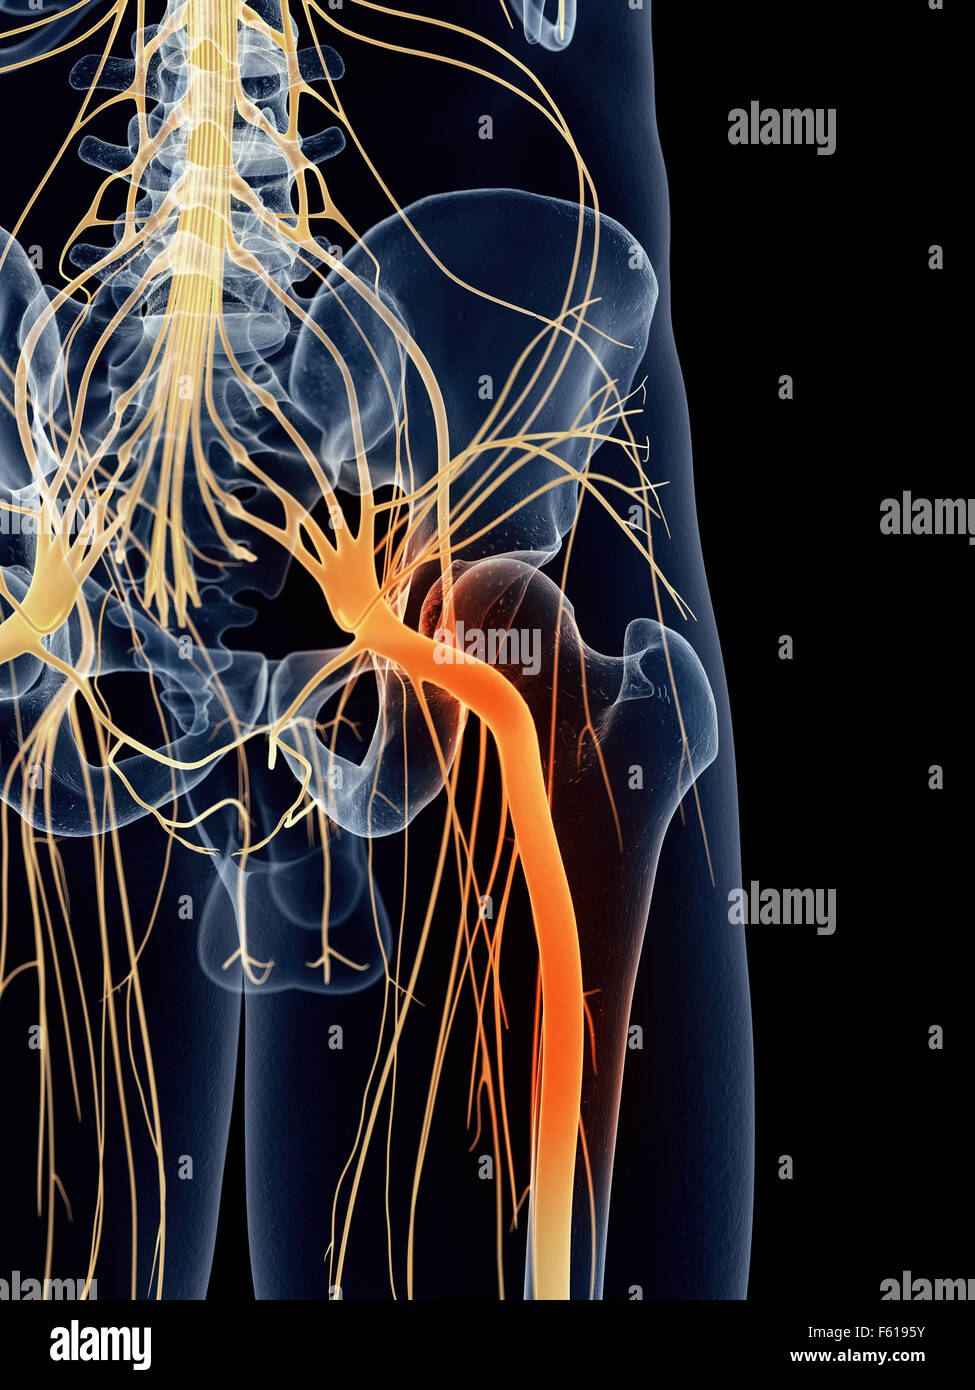

Illustration - médicalement exacts du nerf sciatique douloureux Banque D'Imageshttps://www.alamyimages.fr/image-license-details/?v=1https://www.alamyimages.fr/photo-image-illustration-medicalement-exacts-du-nerf-sciatique-douloureux-89768951.html

Illustration - médicalement exacts du nerf sciatique douloureux Banque D'Imageshttps://www.alamyimages.fr/image-license-details/?v=1https://www.alamyimages.fr/photo-image-illustration-medicalement-exacts-du-nerf-sciatique-douloureux-89768951.htmlRFF6195Y–Illustration - médicalement exacts du nerf sciatique douloureux